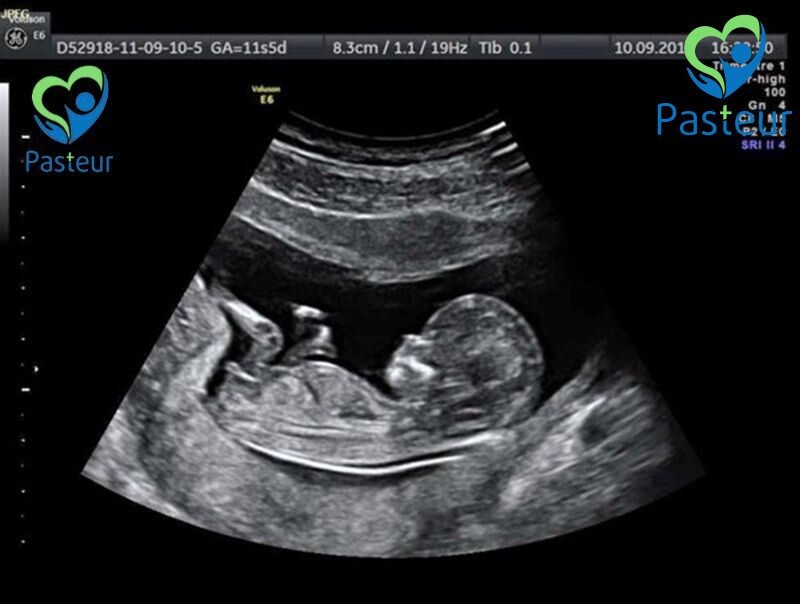

Siêu âm thai là kỹ thuật chẩn đoán y khoa bằng hình ảnh giúp theo dõi thai nhi. Thông qua đó các bác sỹ sẽ theo dõi sự phát triển bình thường của thai nhi hay những phát triển bất thường, các nguy cơ tiềm ẩn.

Siêu âm thai là kỹ thuật sử dụng sóng âm cao tần để ghi lại hình ảnh em bé trong bụng mẹ cũng như các cơ quan sinh sản của mẹ. Thời điểm siêu âm sẽ phụ thuộc vào tuổi thai. Cùng với siêu âm tiêu chuẩn hiện chúng ta đang có một số phương pháp siêu âm tiên tiến bao gồm siêu âm 3D, 4D, siêu âm tim thai. Nhằm theo dõi sự phát triển của thai nhi và phát hiện các bất thường của tim thai.

Về nguyên lý hoạt động và các loại siêu âm này đều sử dụng sóng âm thanh nên đều an toàn. Điểm khác biệt của nó là hình ảnh thai nhi được dựng lên là hình ảnh 2 chiều, 3 chiều hay 4 chiều.

Với siêu âm 3 chiều bác sỹ sẽ nhìn được chiều rộng, chiều cao, chiều sâu thai nhi và các cơ quan sinh sản của thai phụ. Nó đặc biệt hữu ích trong việc chẩn đoán bất thường trong thai kỳ. Còn siêu âm 4D tạo ra một video chuyển động của thai nhi, tạo ra hình ảnh tốt hơn về khuôn mặt và chuyển động của thai nhi.